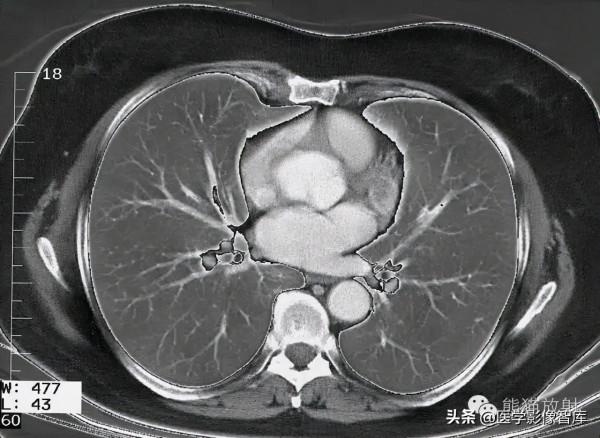

第五層:主動脈弓水平

1. Latissimus dorsi muscle 背闊肌

2. Subscapularis muscle 肩胛下肌

3. Pectoralis minor muscle 胸小肌

4. Pectoralis major muscle 胸大肌

5. Right lung 右肺

6. Rib 肋骨

7. Right brachiocephalic vein 右頭臂靜脈

8. Phrenic nerve 膈神經

9. Sternum (manubrium) 胸骨(胸骨柄)

10. Azygos vein 奇靜脈

11. Thymus 胸腺

12. Trachea 氣管

13. Aortic arch 主動脈弓

14. Left lung 左肺

15. Intercostal muscle 肋間肌

16. Thoracodorsal artery 胸背動脈

17. Infraspinatus muscle 岡下肌

18. Scapula 肩胛骨

19. Spine of scapula 肩胛岡

20. Rhomboid muscle major 菱形肌

21. Trapezius muscle 斜方肌

22. Sympathetic trunk 交感幹

23. Erector spinae muscle 豎脊肌

24. Spinal cord 脊髓

25. Thoracic vertebra 胸椎

26. Thoracic duct 胸導管

27. Esophagus 食管

28. Teres major muscle 大圓肌